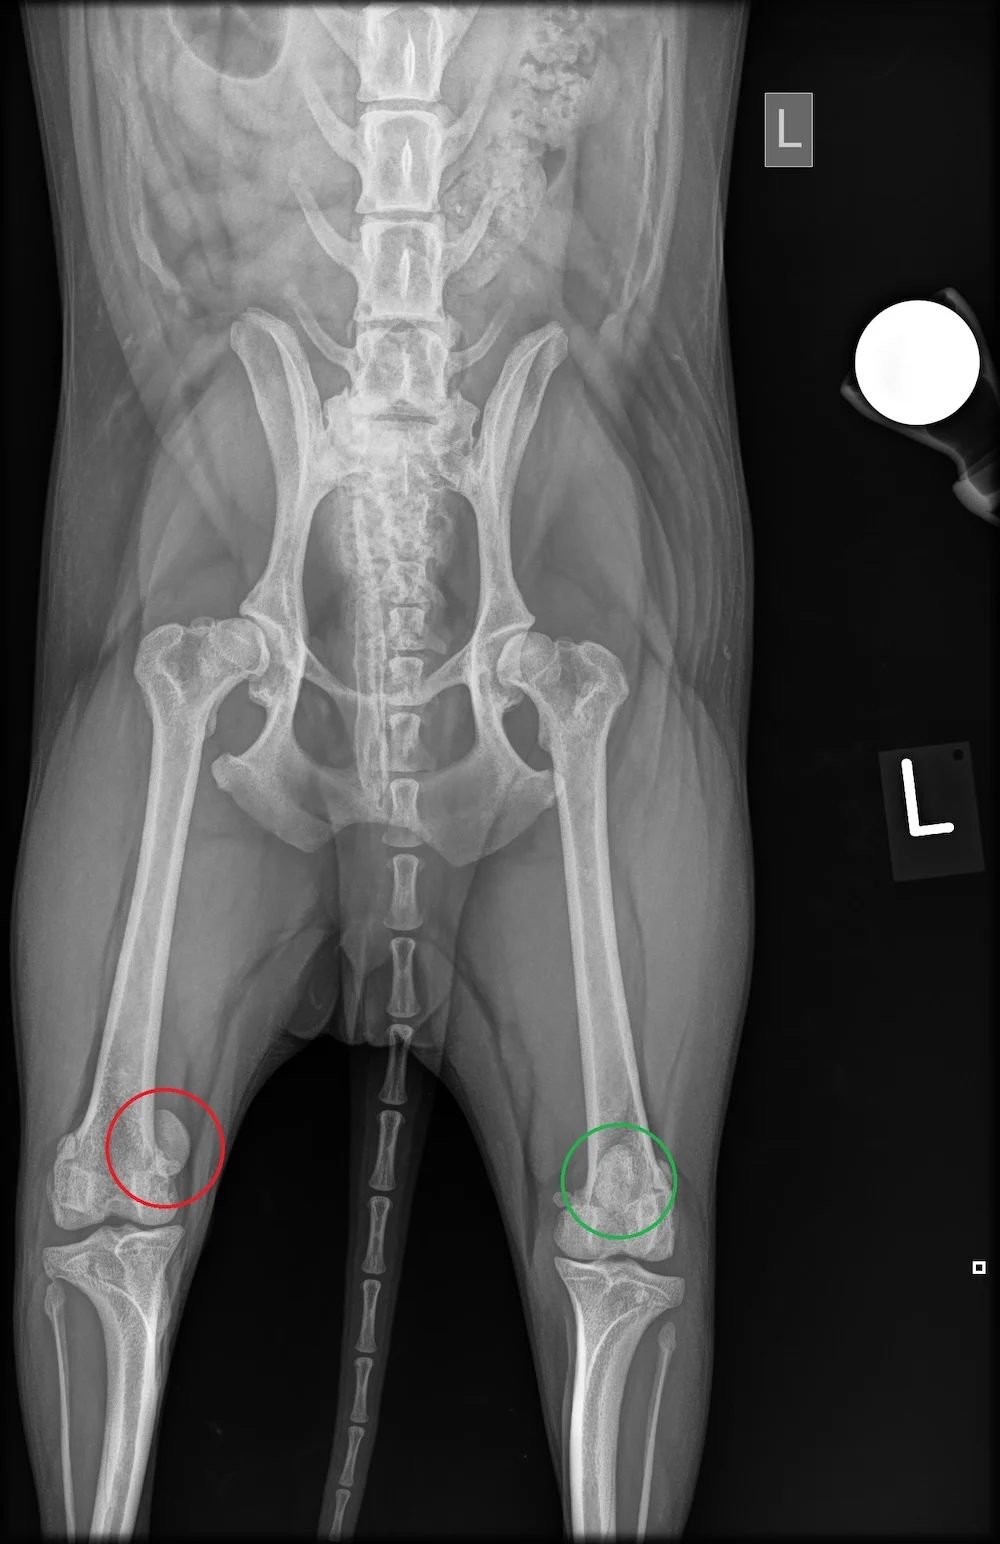

The kneecap, or patella, normally glides in a groove of the femur near the knee. If it jumps out of this groove during movement, it’s called a luxation. This dislocation disrupts motion briefly – seen when the dog suddenly lifts or avoids weight on a leg. Depending on the severity (Grade 1–4), the impact varies. Early diagnosis is key to preventing long-term damage.

x-ray